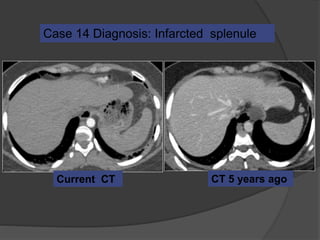

Case 14: 24 F with left sided pleuritic chest pain

CT 5 years ago

CT 5 years agoCurrent CT

Case 14 Diagnosis: Infarcted splenule

Infarcted splenule

 Accessory spleen (splenule ) : failure of fusion of the splenic

anlage, seen in up to 30% of autopsies

 Occur on vascular pedicles and thus at risk for torsion

 Differentiate from polysplenia and splenosis. Identify an intact

spleen, no other splenic foci and normal situs

 Recognize this entity as a cause of abdominal pain that can be

managed non-surgically

Emerg Radiol (2007) 14:123-125